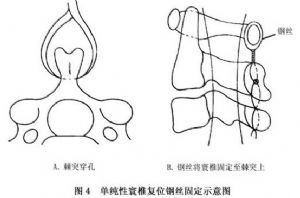

14.3.1 单纯性寰椎复位加内固定术

单纯性寰椎复位加内固定术即从后路暴露术野,将寰椎向后方牵出,并用中粗钢丝(最好是钛丝)将其固定至颈2及颈3的棘突上。以钢丝采取穿过棘突根部的方式更为理想,并酌情于颈1~2之间放置植骨块(图4,5)。但这种方法易失败,主要是因钢丝固定力度欠佳,且易断裂或引起骨折而失败。